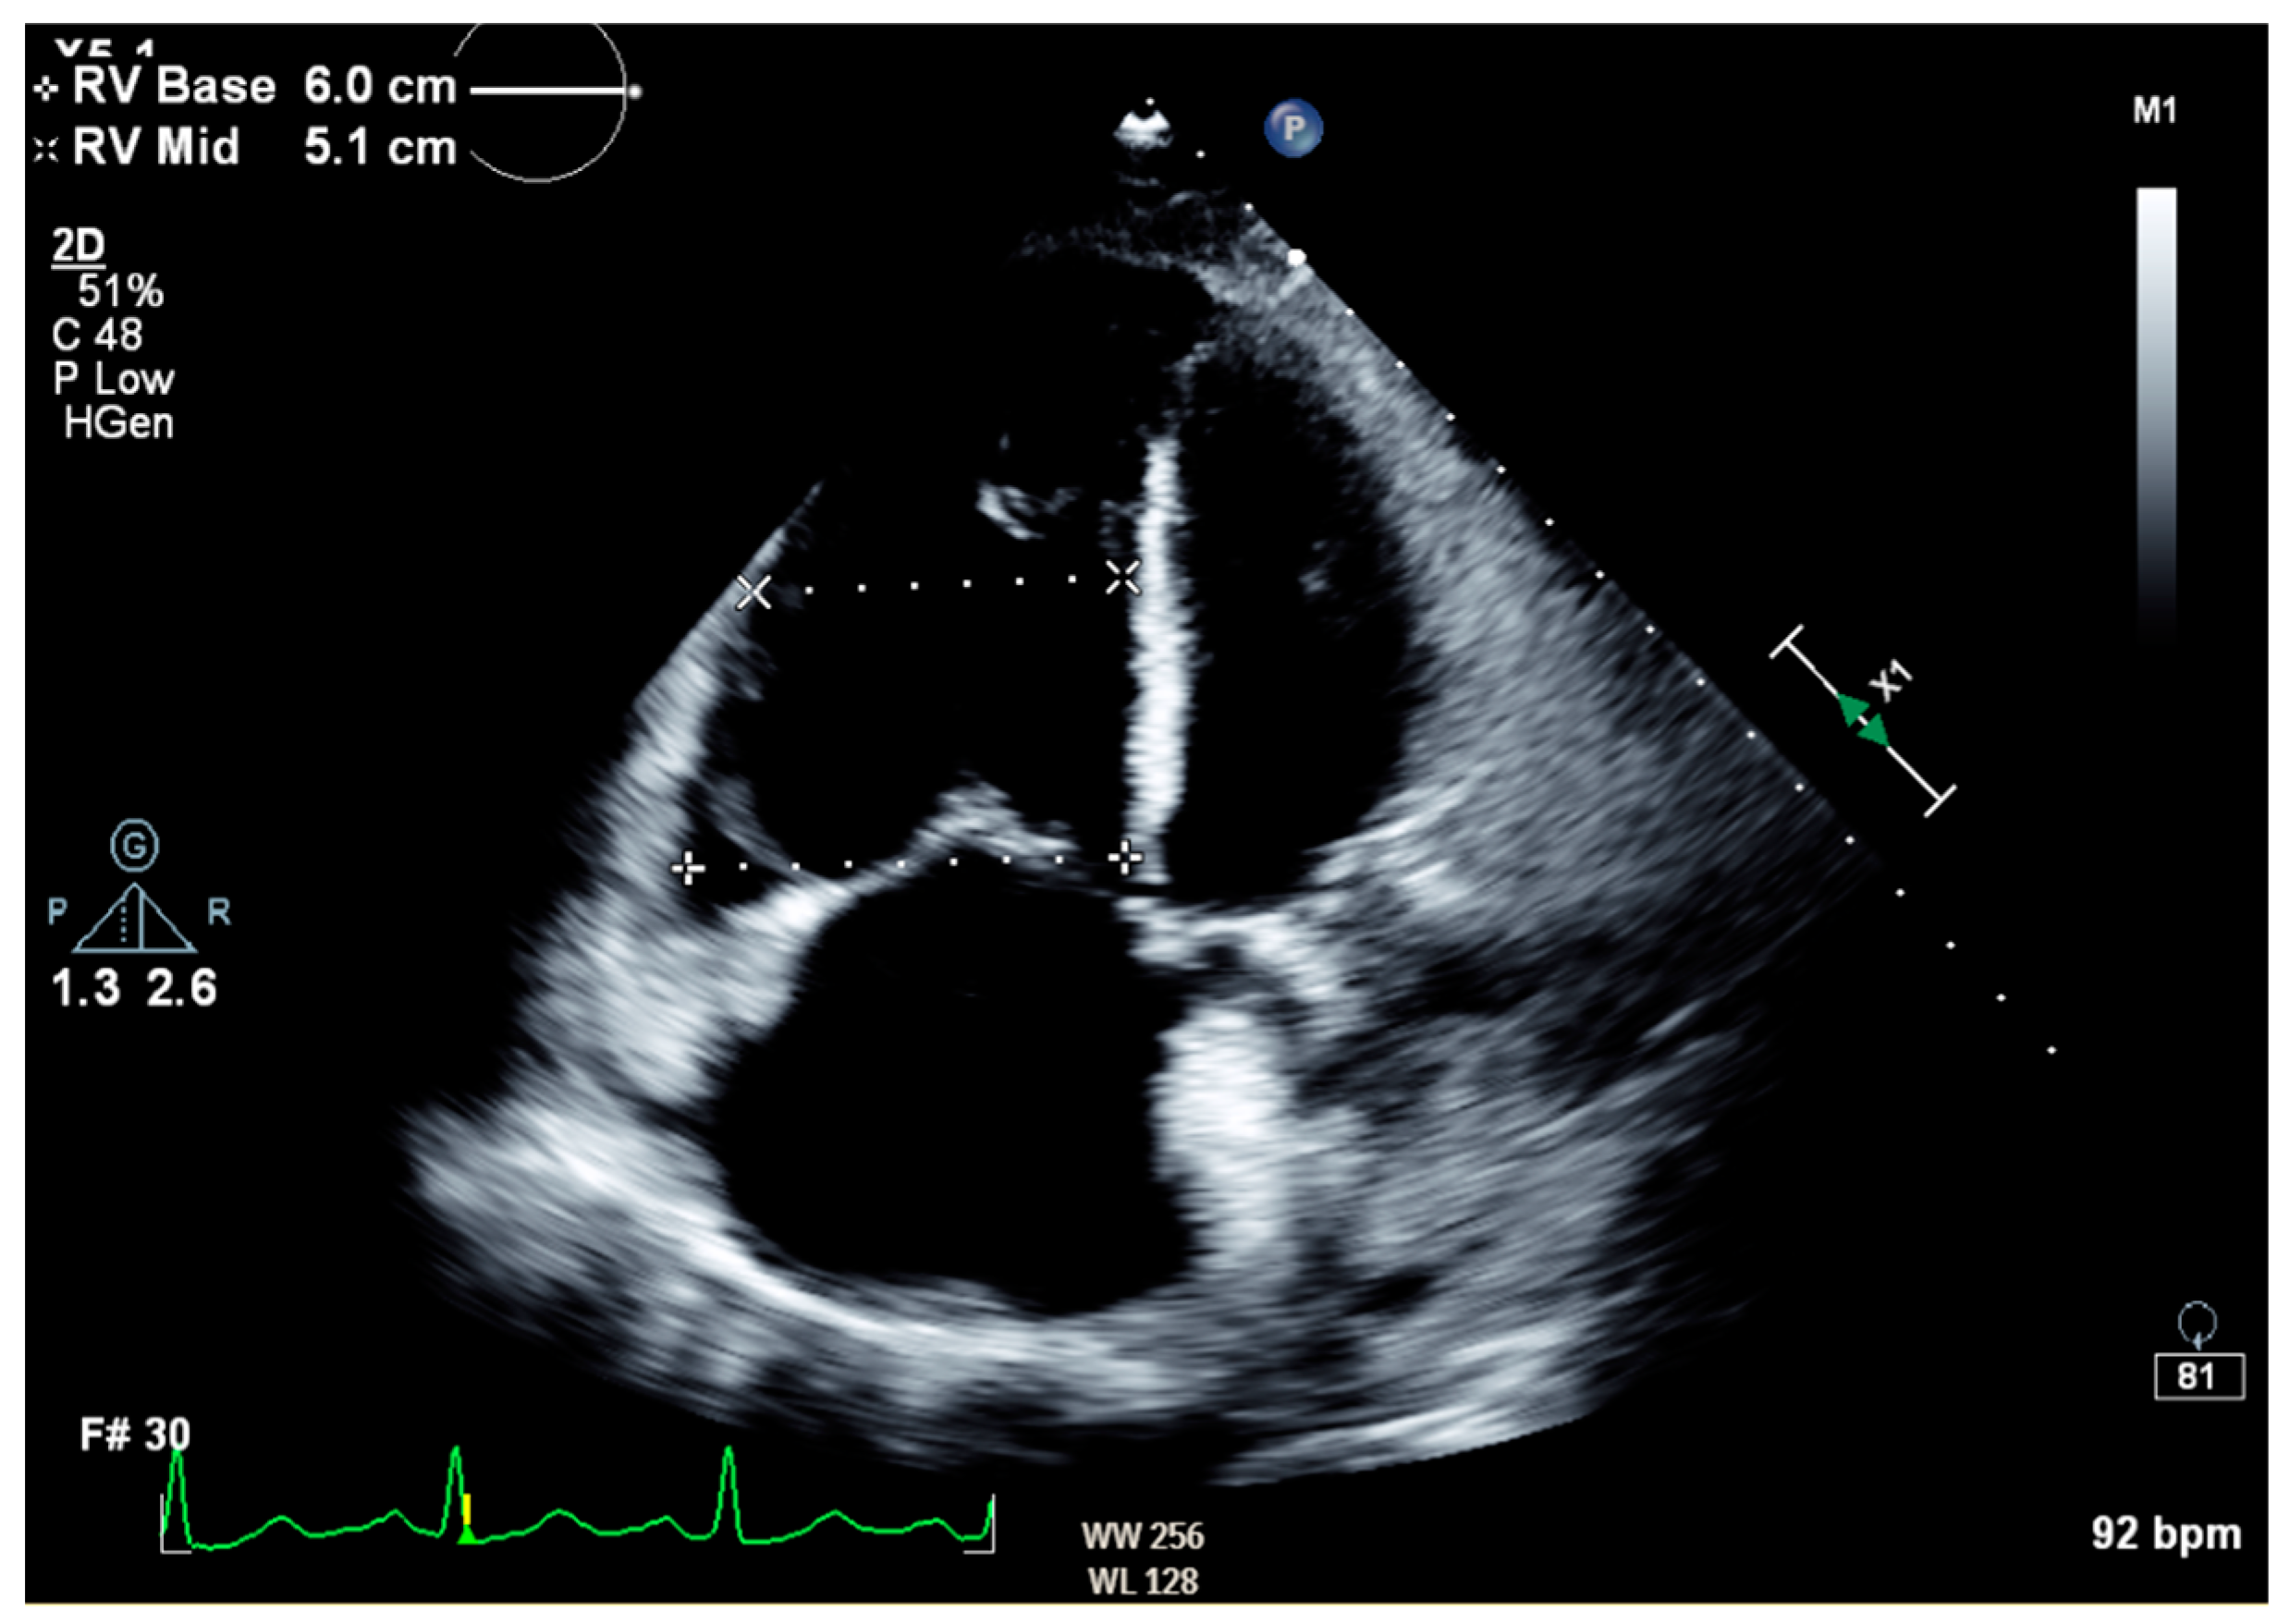

Notable normal admitting lab values included the following: aspartate aminotransferase, alanine transaminase, alkaline phosphatase, bilirubin, platelet count, and international normalized ratio. Creatinine on arrival was 0.79 mg/dL and white blood cell count was 6.0 cells/μL. The only noteworthy abnormal lab was an elevated brain natriuretic peptide of 864 pg/mL. Venous blood gas on arrival with pH of 7.353, pCO2 55.9 mmHg, HCO3 31.1 mmHg, and pO2 21 mmHg. Large-volume paracentesis was performed (5 L), with fluid analysis revealing a serum–ascites albumin gradient (SAAG) of 1.2 g/dL and total protein of 2.6 g/dL. The total nucleated cell count was 1020 cells/mm3 with a polymorphic nucleated cell count (PMN) of 663 cells/mm3, consistent with SBP. The bacterial culture of peritoneal fluid did not grow any organism. An abdominal ultrasound revealed nodular contours within the liver and heterogeneous echotexture compatible with cirrhosis (Figure 1). Doppler imaging of the liver showed patent vessels. Repeat TTE on this admission showed a preserved EF of 65% with paradoxical septal motion, flattened interventricular septum, and severe right ventricular (RV) enlargement consistent with RV pressure/volume overload. The pulmonary systolic pressure was estimated at 74 mmHg (Figure 2). Additionally, the patient was found to have moderate tricuspid regurgitation with a maximum velocity of 385 cm/second (Figure 3).

Figure 1. Liver ultrasound in right long axis demonstrating nodular contours with coarsened echotexture. Moderate volume ascites can also be seen.